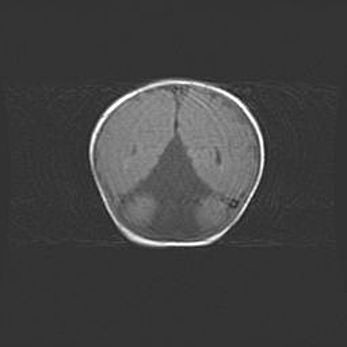

Наружная гидроцефалия с возможной атрофией височных областей.

Возраст: 28 дней

Вес: 3670 г

Пол: мужской

Окружность головы: 38 см

Срок гестации: 40 недель

Гидроцефалия головного мозга у новорожденных – это заболевание, которое характеризуется скоплением избыточного количества спинномозговой жидкости в желудочковой системе головного мозга в результате затруднения её перемещения от места выработки к месту поглощения в кровеносную систему или вследствие нарушения абсорбции. При открытой наружной форме гидроцефалии у новорожденных расширяются и переполняются субарахноидные пространства.

При нормотензивных  формах,  которые,  как  правило,  являются  следствием  перенесенных ишемических  повреждений  паренхимы  мозга,  возможно  сочетание микроцефалии  с нормотензивной гидроцефалией. В основе данных изменений лежит атрофия больших полушарий с преимущественной  локализацией  в  лобно-височных  областях.